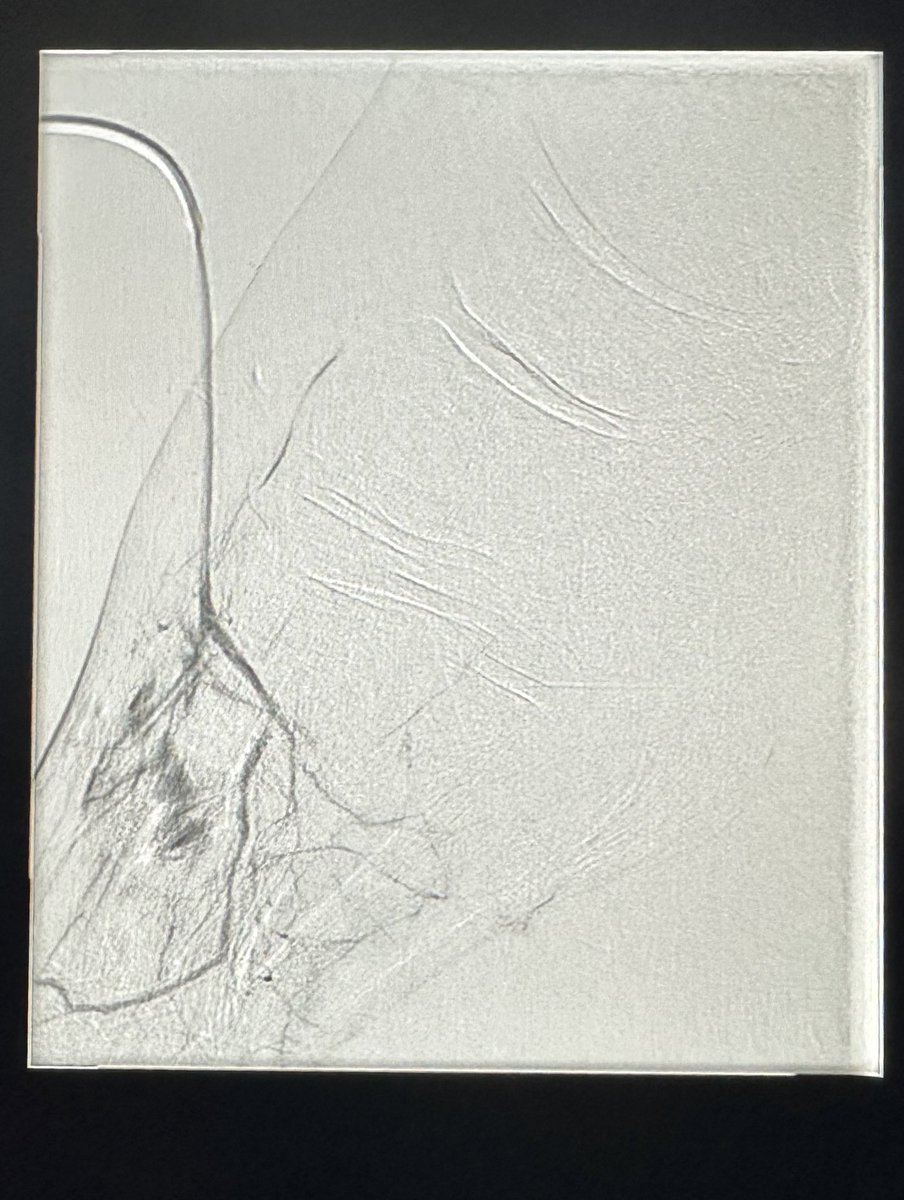

حالة من حالات نقص التروية الدموية الحاد مع وجود جرح غير ملتئم في القدم تم علاجها في وحدة #الأشعة_التداخلية بجامعة الملك سعود بالدخول من شرايين الفخذ والكاحل و إعادة فتح و توسيع الشرايين @ksumedicalcity @_KSU

د.سلطان رباح الحربي | Dr. Sultan R.Alharbi tweet mediaد.سلطان رباح الحربي | Dr. Sultan R.Alharbi tweet mediaد.سلطان رباح الحربي | Dr. Sultan R.Alharbi tweet mediaد.سلطان رباح الحربي | Dr. Sultan R.Alharbi tweet media

في وحدة #الأشعة_التداخلية بجامعة الملك سعود نقوم بتوفير أحدث التقنيات لعلاج القدم السكرية ونقص التروية. الدخول للشرايين يتم من الفخذ ، أو في بعض الحالات المتقدمة من الكاحل أو حتى من اخر القدم. بعض التقنيات لا توجد الا في أماكن قليلة جداً بالشرق الأوسط @ksumedicalcity @_KSU @ksu_medicine @FcmKsu